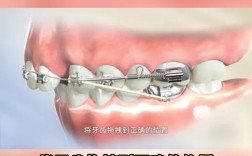

牙套更换频率:

标准的更换频率是每1-2周一副,对于一些需要更精细控制的移动,医生可能会建议使用更薄的牙套(如Invisalign G6或类似技术)或更频繁的更换(如每周一副),这可能略微加快速度,但需在医生指导下进行。

- 骨钉(微种植钉): 提供更强的支抗,帮助移动牙齿(如压低、远移),有时能缩短时间。